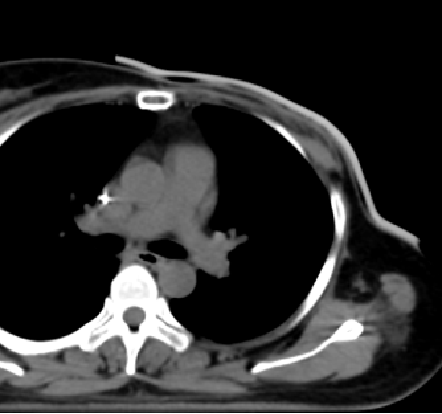

乳腺癌患者经乳房切除术后,往往需要辅助放射治疗提高生存率和局部控制率。在术后辅助放疗方案中,基于X射线的调强放射治疗技术得到广泛应用。由于乳腺癌患者在接受乳房切除术后,胸壁皮肤和皮下组织是高危复发区域,而X射线在皮肤表面有剂量建成效应,这种效应会导致皮肤表面剂量不足。因此,需要在皮肤表面添加组织补偿物上移剂量建成区,提高皮肤表面剂量。

相较于临床上常用的通用等效膜,3D打印技术制作的个性化组织补偿膜优势明显:这种组织补偿膜依据患者CT定位数据1:1还原制作,与皮肤高度贴合,增加摆位重复性,减少气隙显著提升了放疗精准度此外,3D打印组织补偿膜具有良好的均匀性、适形性、生物等效性和可重复性,保证了治疗效果的一致性。

该技术适用于乳腺癌术后胸壁较薄、表面不平、乳房重建等患者,通过3D打印补偿膜获得更精准的放疗剂量分布,从而提升治疗效果,减少副作用,为患者带来了更优质的医疗服务。